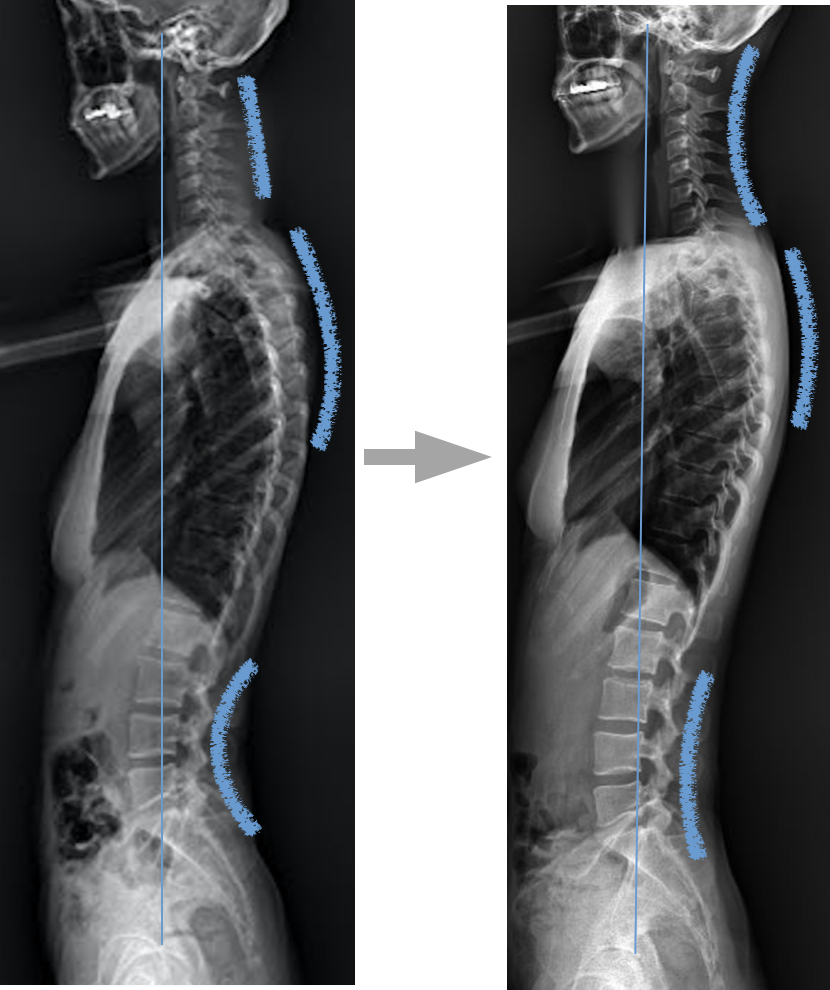

척추 만곡에도 변화가 생기는데요. 이 또한 엑스레이 사진에서 변화를 확인할 수 있습니다.

1. 교정 전에는 일자목에 가까운 경추의 커브가 교정 후 C자 커브로 변화되었습니다.

2. 흉추가 후만되어 있으며 어깨의 견봉이 앞으로 이동해 있어 어깨가 앞으로 말려있었는데요. 흉추부의 커브도 변화가 생겼습니다.

3. 요추의 만곡이 완화되면서 요추부의 위치가 이동한 것이 관찰됩니다.

4. 천골도 후만되어 있었는데 천골의 위치도 변화가 생겼습니다.

5. 척추의 만곡이 정상화되면서 늘 뭉치던 어깨가 편해지고 만성적인 편두통도 호전됩니다.